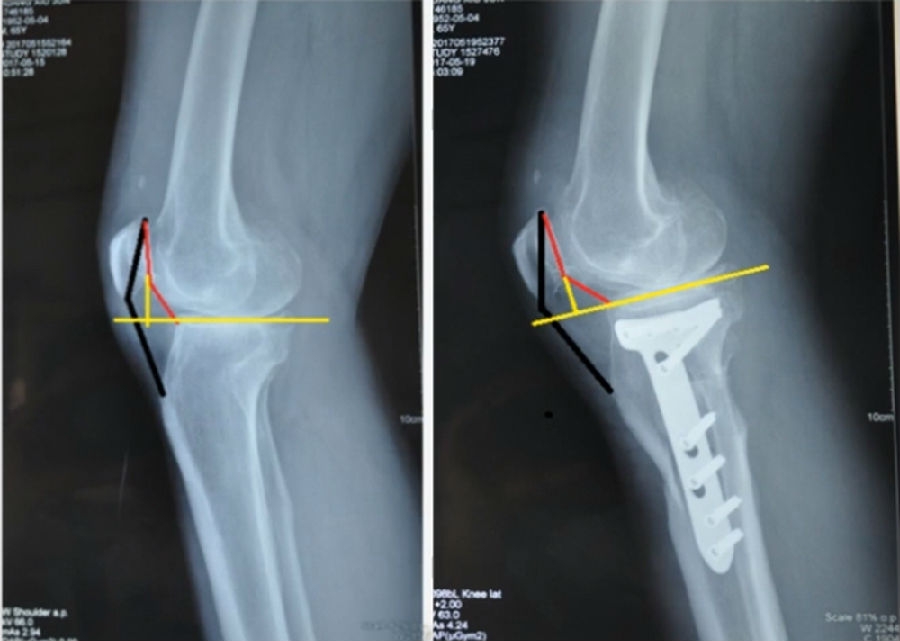

典型病例,女性,56岁,农民右膝内翻18度。

术前影像

术中影像

结合影像学来看,该患者单纯用闭合截骨或开放截骨,对肢体均有影响,所以决定采用混合型截骨。术中混合截骨旋转中心选在内外1/3处,先做闭合楔,然后顺势将开放楔敲开,达到术前设计的目标力线。术后随访力线达到要求。

术后X线

术后检查证实达到了术前预期的手术效果,关节线达到了平行,半脱位得到矫正,同时关节线和地面水平。病人行走达到了理想的效果。

患者术后4个月截骨愈合,膝关节稳定维持得非常好。

术后4个月